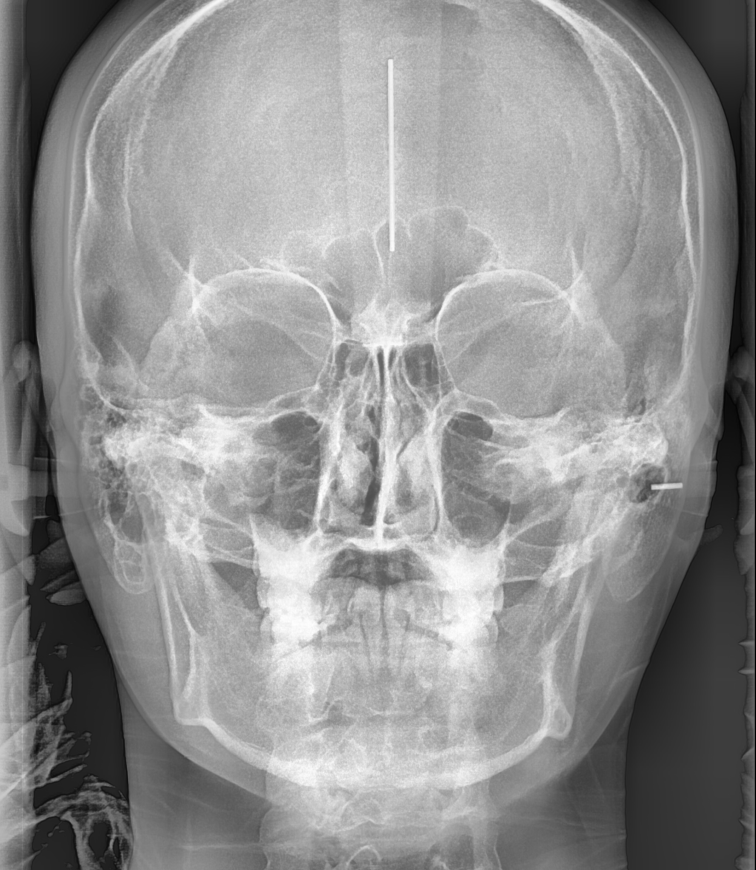

초진 상담 후, 보다 정확한 진단을 위해 정밀 검사가 진행됩니다.

250207 교정할때만 찍는 X-RAY 사진이죠~

파노라마, 세팔로

연령에 따라 손 사진을 찍기도 하고요~

치아를 본떠 현재 치아 모양을 분석합니다!

분석할 내용이 이렇게 많아요!!!